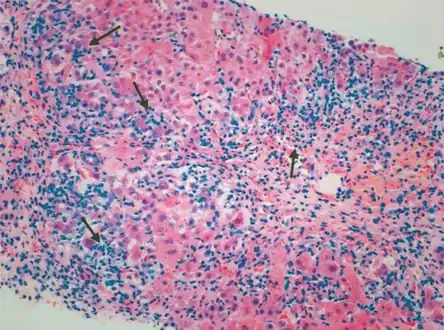

Giant cell transformation in autoimmune hepatitis

Portal and periportal inflammatory infiltrate- interface hepatitis (piecemeal necrosis) arrow(s)